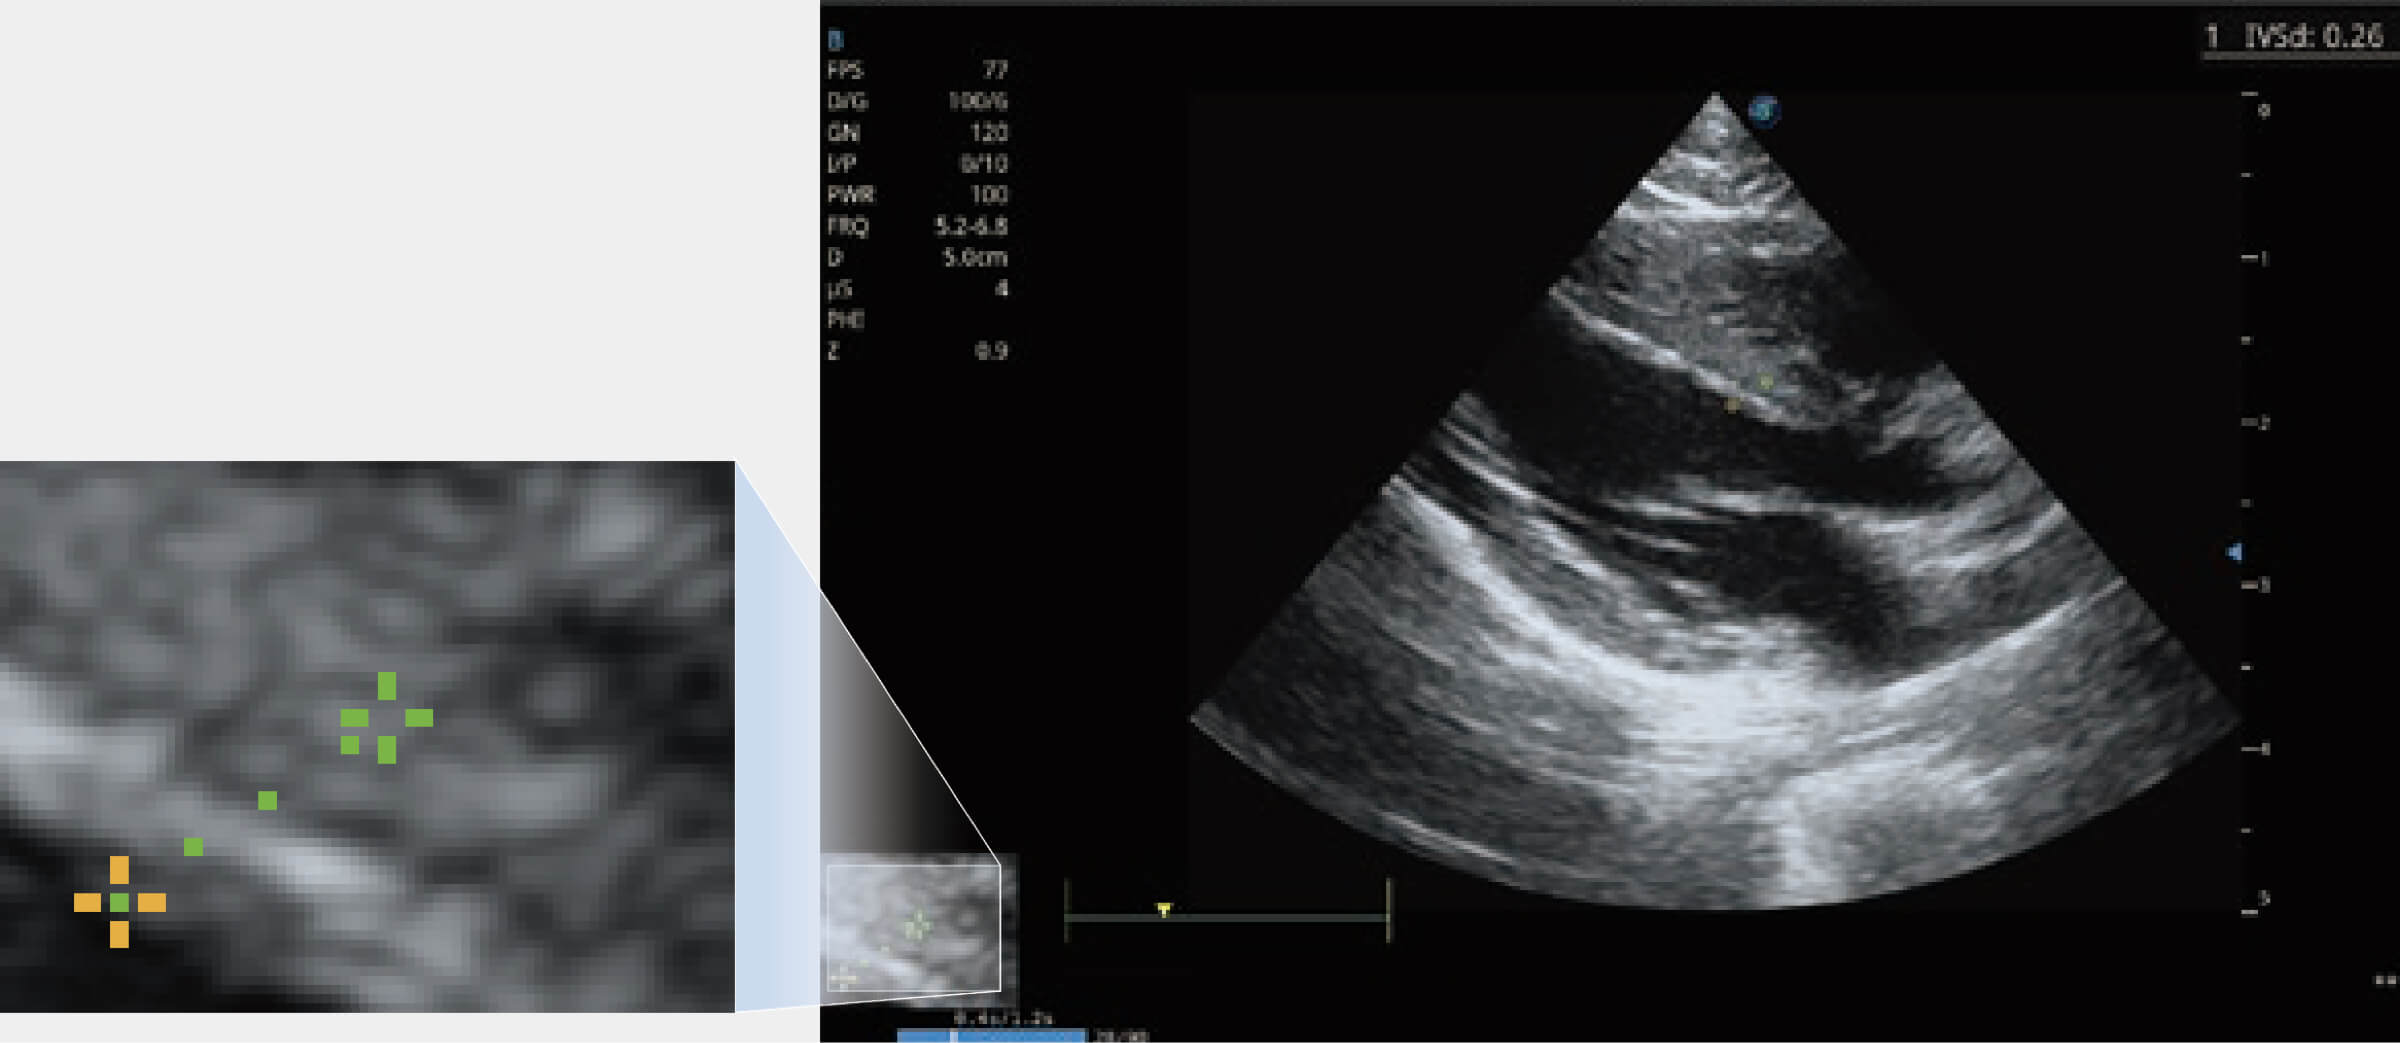

通過360度任意調(diào)節(jié)3條M型取樣線,在同一心動周期上觀察心臟不同位置的運(yùn)動曲線,得到準(zhǔn)確的心功能測量數(shù)據(jù),有效評估心肌運(yùn)動及左心室功能。

提供解剖示意圖、標(biāo)準(zhǔn)超聲圖像、掃查手法涂和操作者實(shí)時檢查圖像,指導(dǎo)操作者進(jìn)行標(biāo)準(zhǔn)切面的正確掃查。